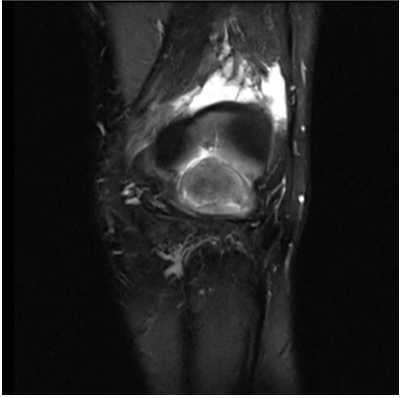

Cyclops Syndrome: A Rare Cause of Postoperative Knee Extension Loss

Ouijdane Zamani, Bassel Saber, Rachida Saouab, Jamal El Fenni, Meryem Boui and Meryem Edderai. 17(1): 01-03.